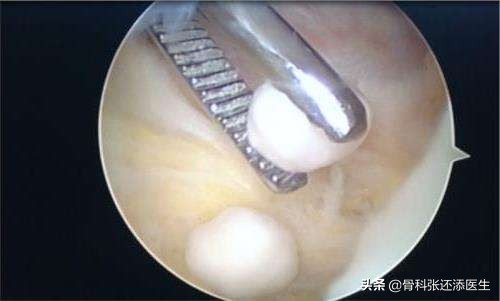

3.另外呢,关节内游离体(关节内的废物,如骨赘,损伤脱离的半月板碎片等)也可以是主因。这个时候患者走路可能有卡压,“积液”是因为游离体在关节腔游动,加剧磨损及积液产生导致。

这个需要关节镜手术治疗。不能让这个小老鼠坏了一锅汤啊~

关节镜手术下,摘除游离体,有点像掏鸟蛋